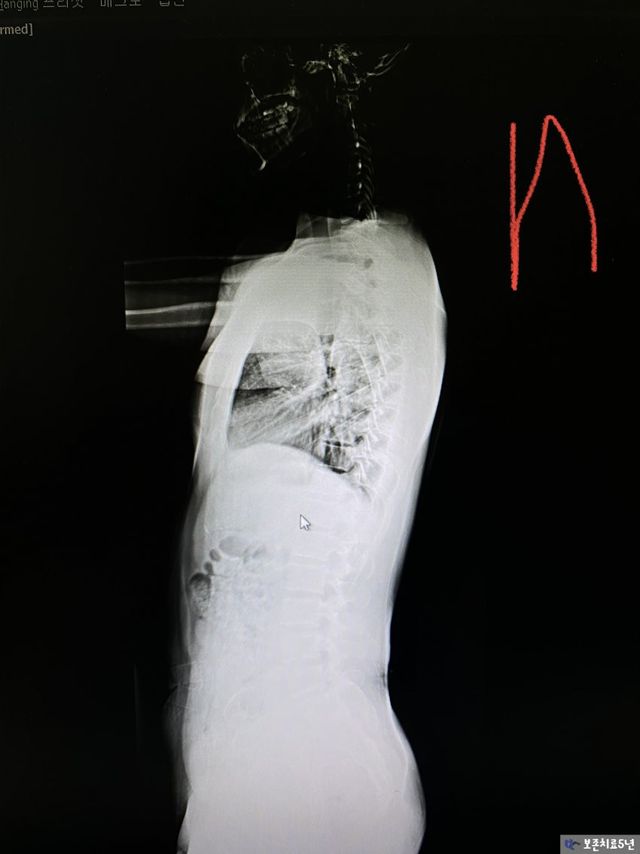

2. 통증 히스토리

20대부터 날개뼈, 익상견갑, 목통증에서 허리통증으로 연결 되었고 골반통증에서 허리디스크 까지 결국 왔다.

이렇게 버티다가 결국 원인을 못 잡으니 결국에는 취준 준비하다가 허리디스크로 입원하고 시술했다.

나는 X자 다리에, 편평등이 심했으며, 평발까지 있었음. 이 상태로 골반중립 없이 운동을 하다보니